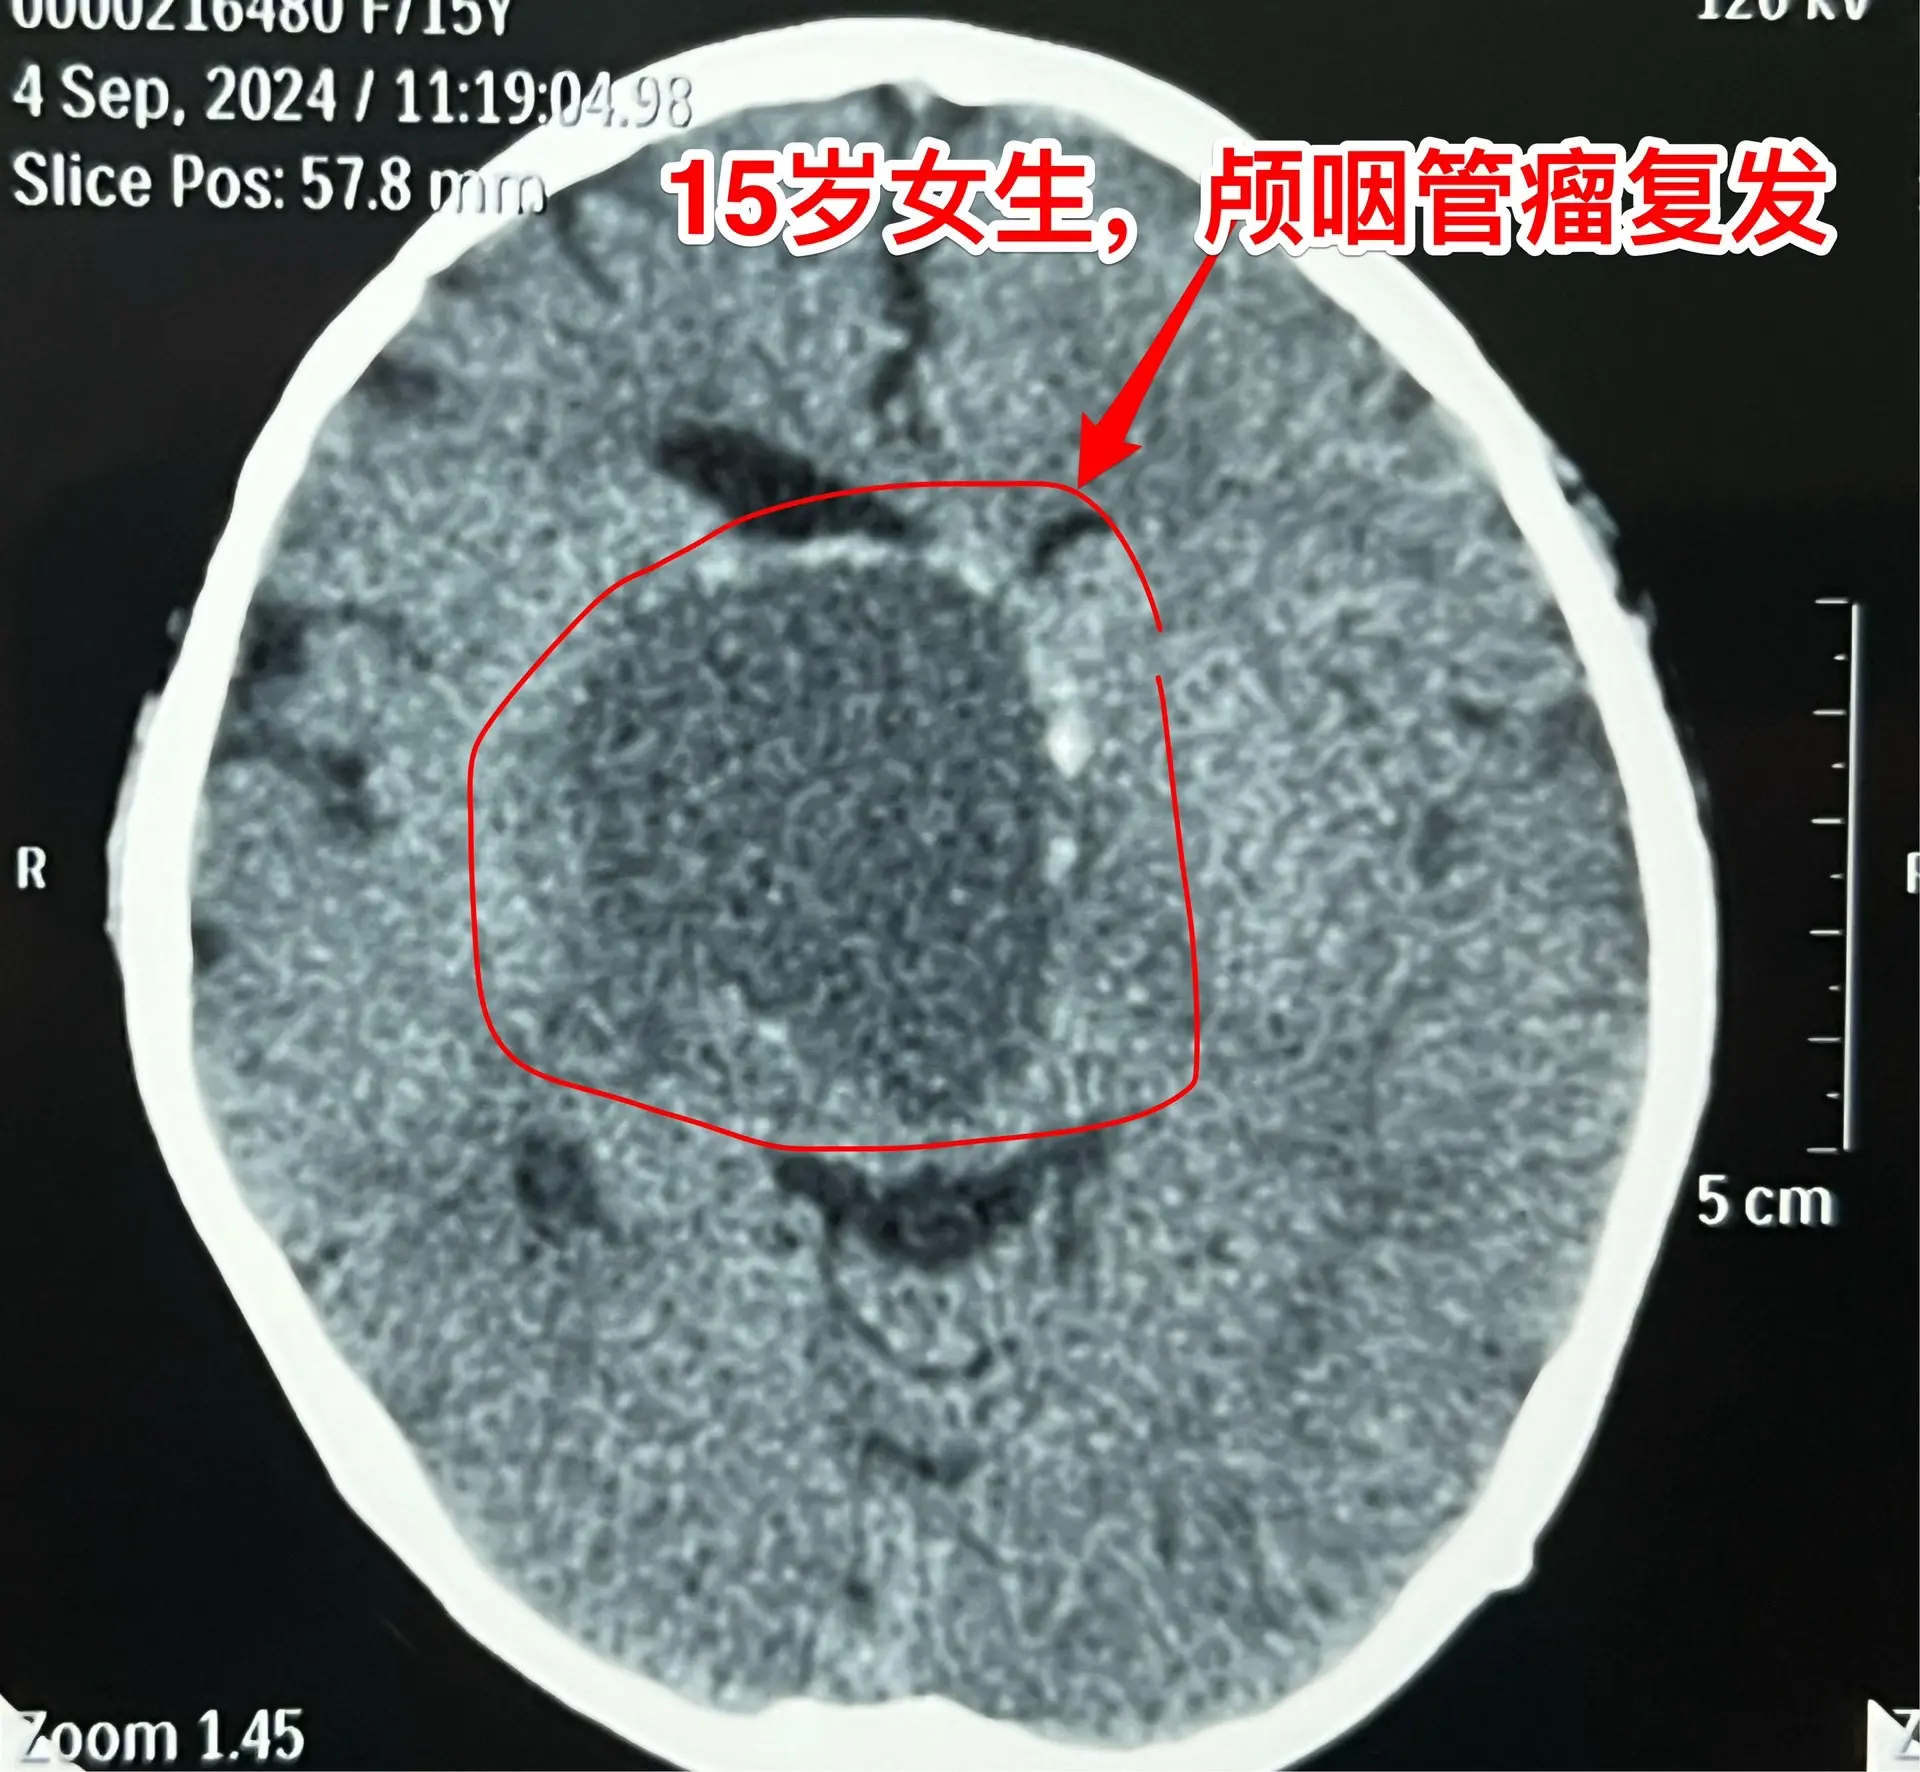

颅咽管瘤不是按匀速生长,进展很难预料。15岁的福建龙岩市女生,因颅咽管...